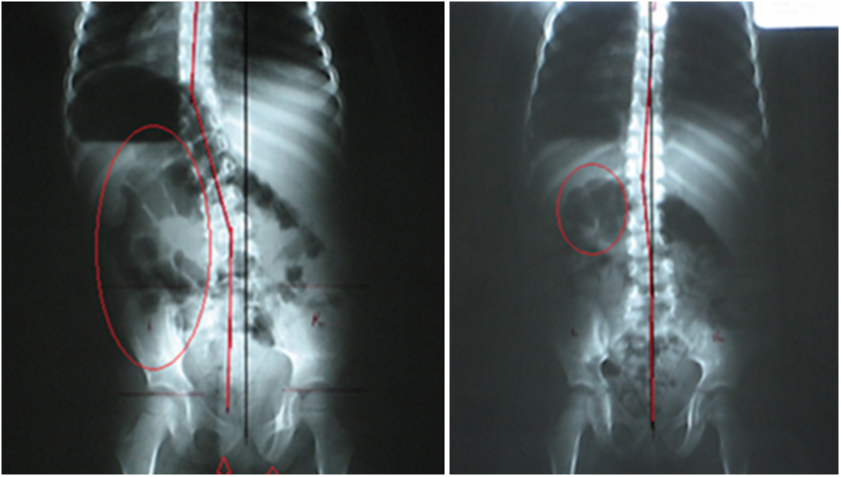

2. DIGITAL SPINAL RADIOGRAPHY

PRS also utilizes static X-ray, to provide precise, spinal alignment studies and rule out pathologies.

By providing a clear baseline for further diagnosis and care, static X-rays enable chiropractors to develop targeted strategies tailored to each patient’s needs.

Serving as the cornerstone for our more advanced technologies and techniques, this method ensures a solid starting point, empowering practitioners to build upon accurate data for optimal spinal correction and lasting patient outcomes.